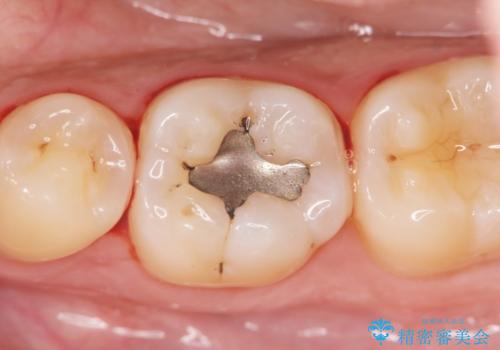

「セラミックインレー」目立つ下顎の銀歯を白くしたい

- 長年色が気になっていた銀歯を白くしたいと希望され来院されました。

丁寧に拡大鏡下で銀歯を除去し虫歯がないことを確認したのち、シリコンによる精密な型取りを行いセラミック修復物を作製します。